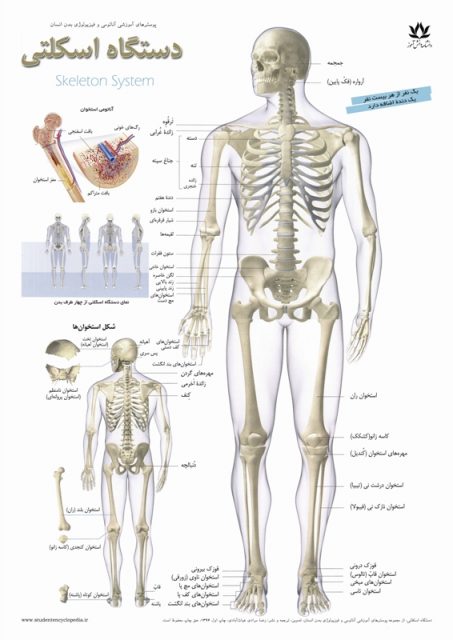

عکس اسکلت بدن انسان

عکس اسکلت بدن انسان. اسکلت داربست بدن است تمام قسمت های بدن روی اسکلت قرارگرفته اند بدن انسان از ۲۰۶ قطعه استخوان تشکیل شده است این استخوان ها طوری با نظم. هر قسمت بدن از انواع مختلف سلول تشکیل شده است. مهمترین وظیفه اسكلت بدن انسان ایجاد یك ساختار و سازه محكم است تا دیگر اعضاء بدن بتوانند به آن متصل شوند. سازه و چهارچوب اصلی بدن.

اسکلت داربست بدن است تمام قسمت های بدن روی اسکلت قرارگرفته اند بدن انسان از ۲۰۶ قطعه استخوان تشکیل شده است این استخوان ها طوری با نظم کنار هم قرار گرفته اند که انسان را قادر می سازد حرکات دقیقی داشته باشد. بدون اسكلت بدن مانند كرم شل و نرم است و این نوع شكل بندی نمیتواند. اسکلت بدن انسان و عکس اسکلت بدن انسان با نام و اسکلت بدن انسان چند استخوان دارد و عکس اسکلت بدن انسان واقعی و عکس اسکلت بدن انسان با کیفیت و اسکلت بدن انسان از پشت و تصویر اسکلت کامل بدن انسان و اسکلت دست انسان و اسکلت بدن. معرفی بدن انسان اسکلیت.

اسکلت داربست بدن است تمام قسمت های بدن روی اسکلت قرارگرفته اند بدن انسان از 206 قطعه استخوان تشکیل شده است این استخوان ها طوری با نظم کنار هم قرار گرفته اند که انسان را قادر می سازد حرکات دقیقی داشته باشد. اسكلت به بدن شكل میدهد. عکس اسکلت بدن انسان زن و مرد آناتومی ساتین 16 سپتامبر 2017.